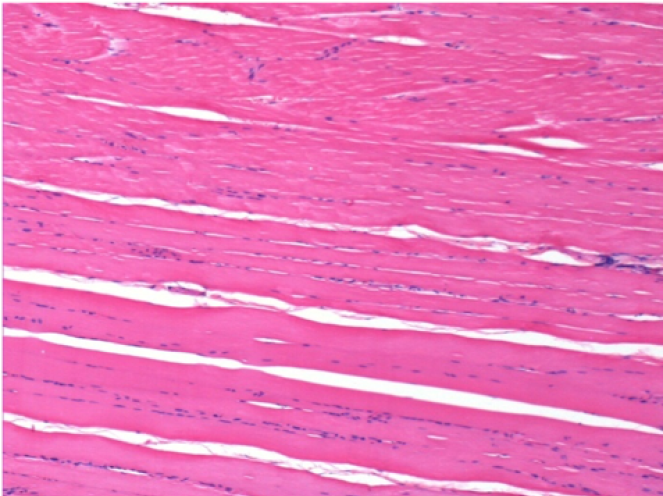

Л: Претибіальний м'яз - без лікування

Через 10 днів після ін'єкції Ендопіл 0,1 мл в правий претибіальний м'яз.

Тут можна побачити утворення вакуолей, які оточені лімфоцитами. Вакуолі відрізняються від некрозу тканини. Присутність лімфоцитів пов'язана з проникністю клітинних мембран.